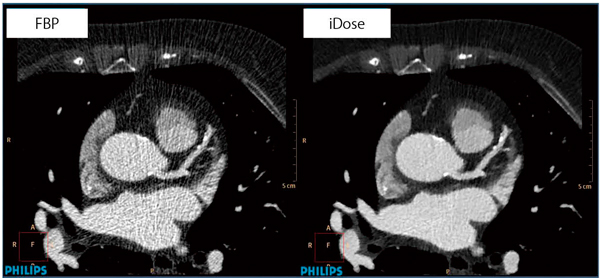

iDose4は,RAWデータレベルから逐次近似計算を行い,さらにアナトミカルモデル,統計学的ノイズモデルの2つのモデルに対して逐次近似計算を行っていく(図2)。これによりノイズだけではなく,CT特有のアーチファクトの発生を抑制することができる(図3)。

図3 iDose4の臨床画像